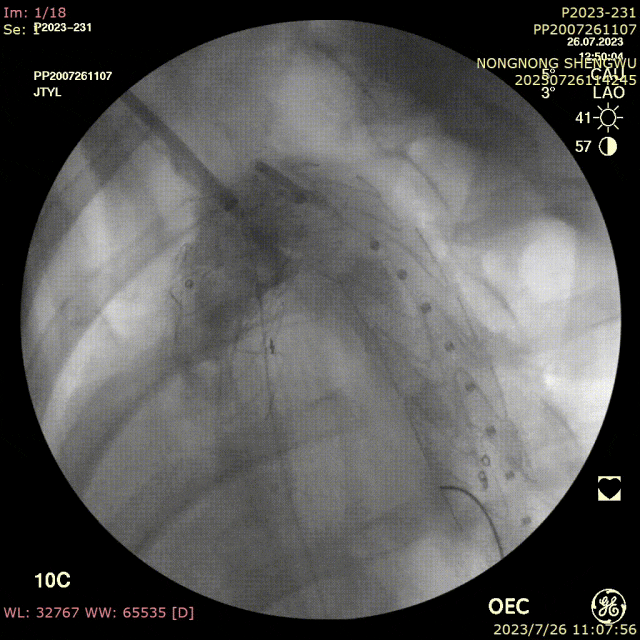

手术过程:

全麻下双上肢穿刺,右股动脉切开,左上肢路径造影,右上肢进保护性导丝,对支架预开窗后植入升主,因破口较大,支架近端掉入破口,远端扭转遮蔽左颈总动脉及头臂干,窗口对破口,再次植入一枚38-80支架,封住近端破口后,以8*60支架开放右侧头臂干,6*10人工血管行右锁骨下-左颈总搭桥,取颈前静脉行左椎动脉-人工血管搭桥,之后造影,头臂动脉均通常,术后约2小时患者清醒。